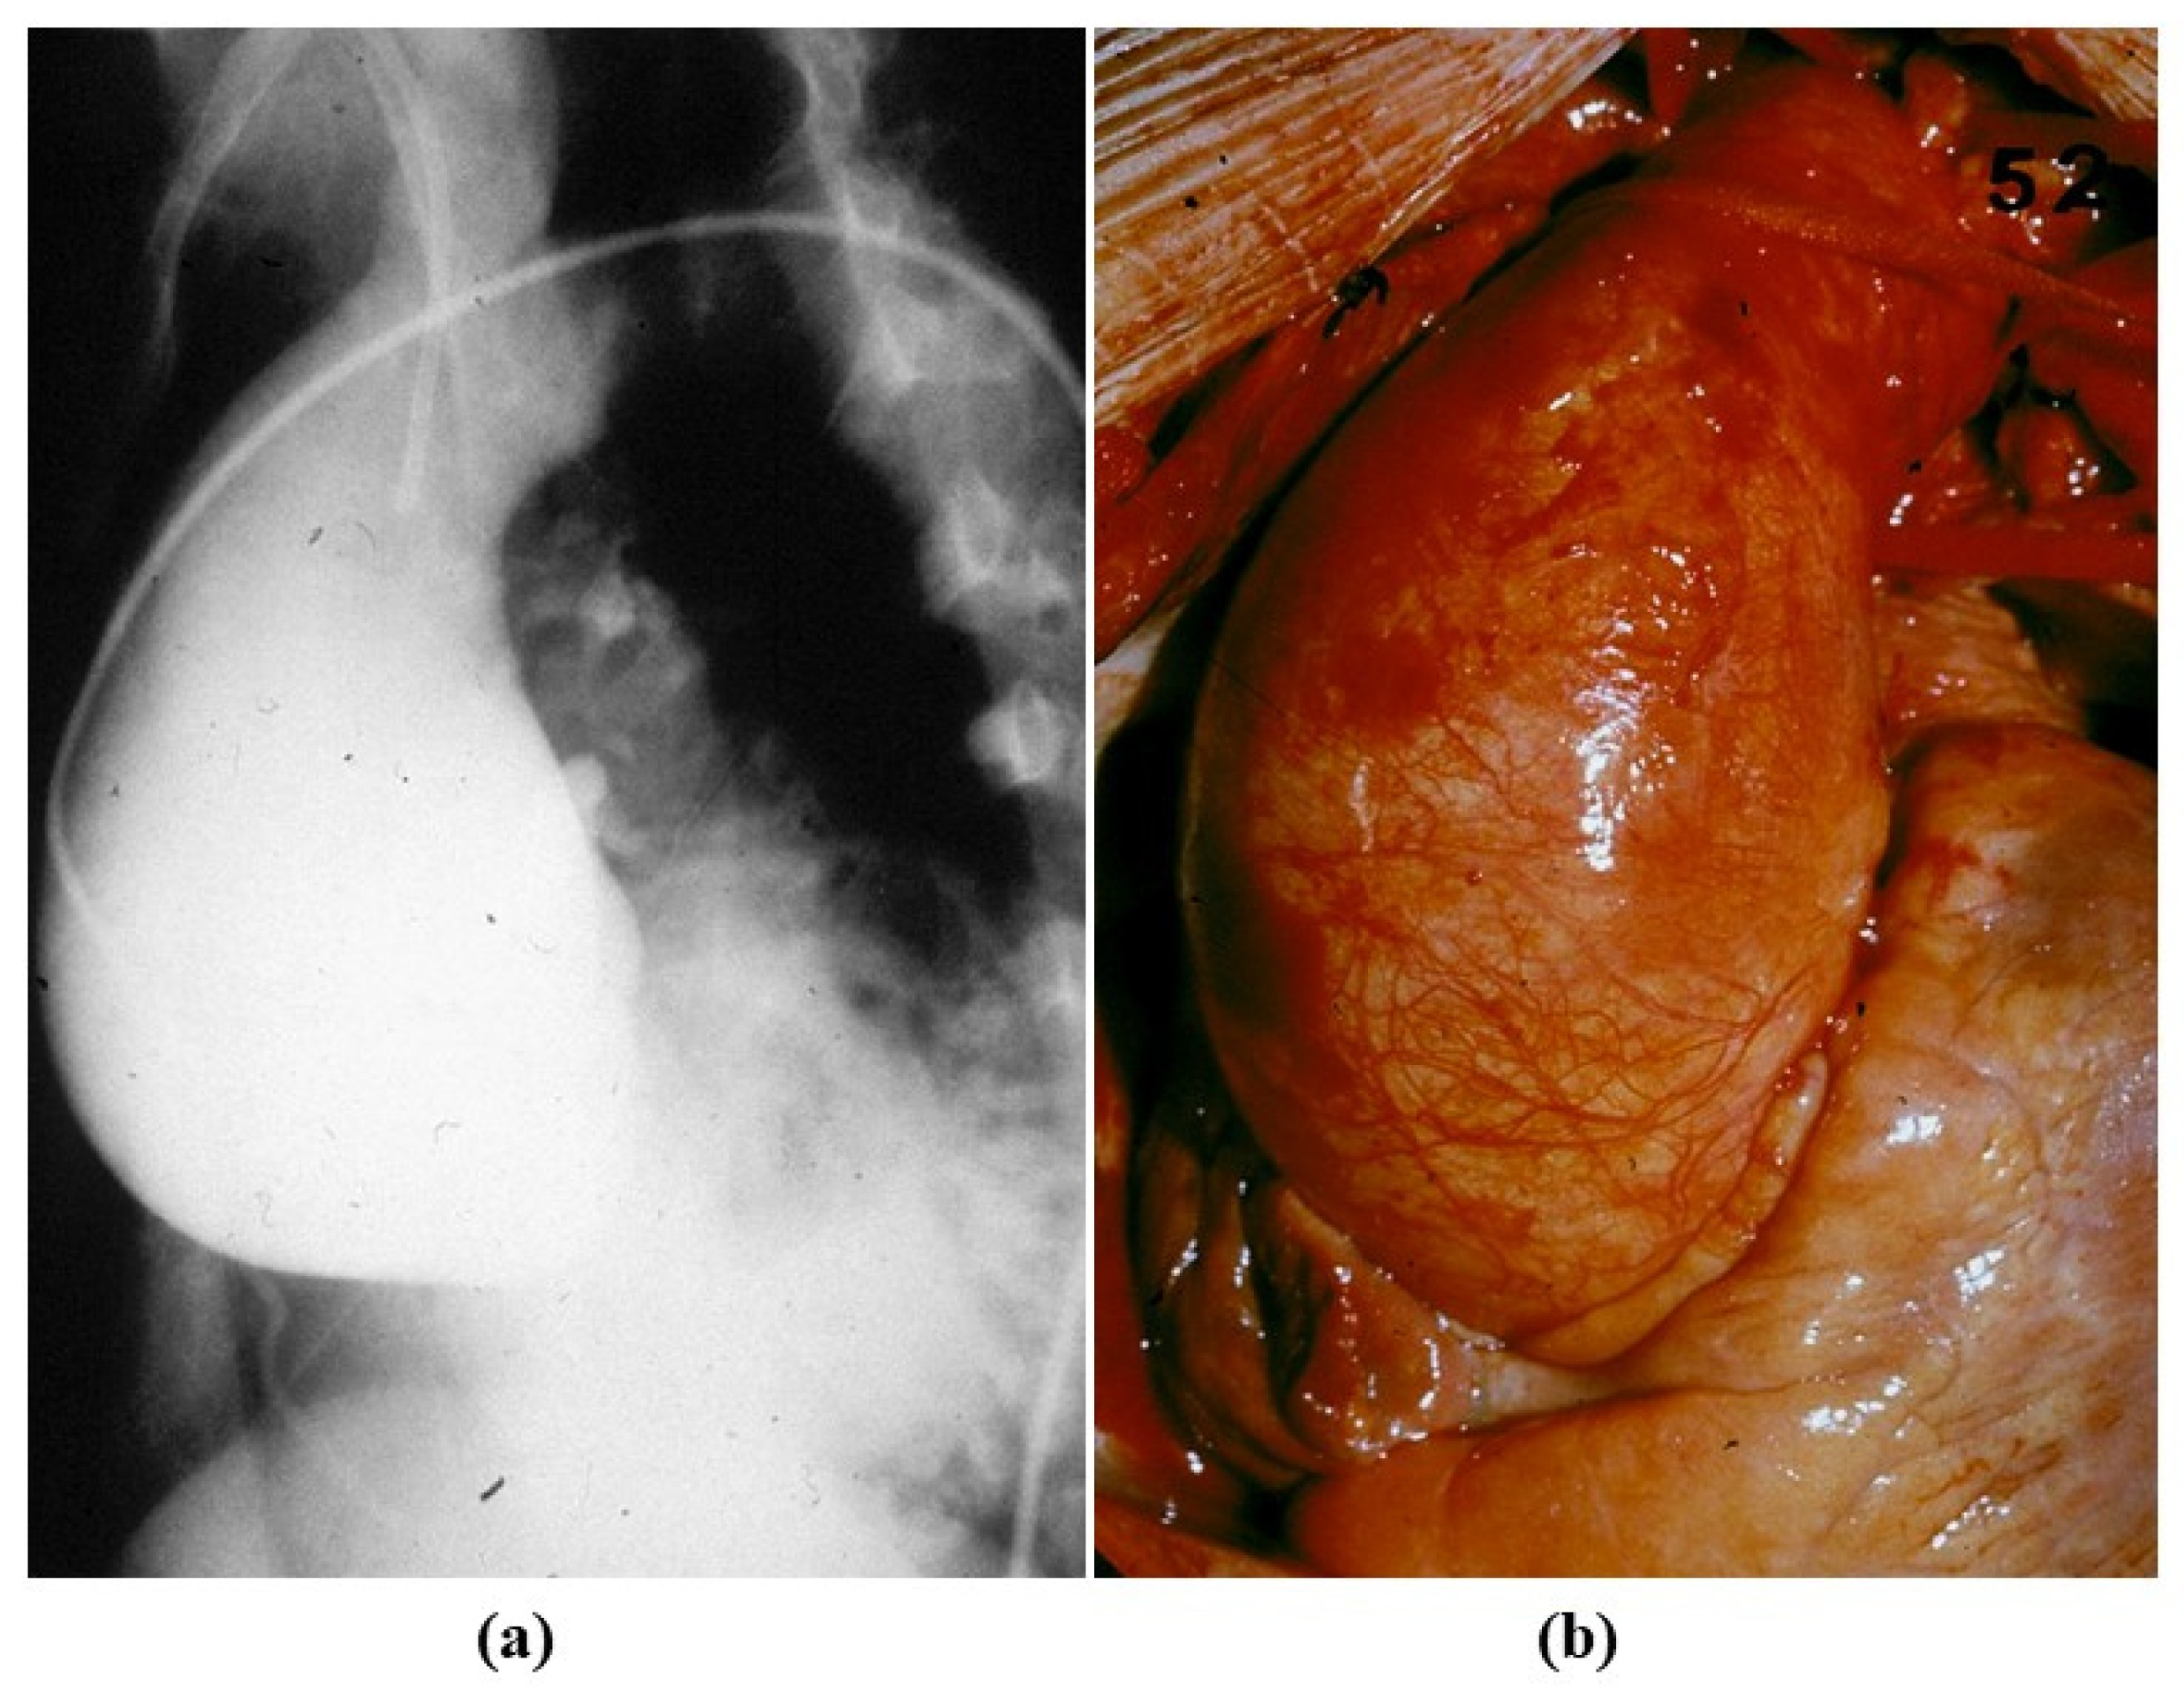

Figure 17. Angiographic (a) and intraoperative (b) gross views of non-inflammatory anuuloaortic ectasia with valve incompetence.

Degenerative disease may primarily affect the tunica media with medionecrosis, elastic fiber fragmentation and an increase in extracellular ground substance in the lamellar units, even in the absence of a genetically determined disorder (Figure 15). It may account for aortic dilatation of the ascending aorta and aortic valve regurgitation, nowadays the most frequent cause of aortic incompetence. Both sinusal [27,28] and tubular portions appear dilated (Figure 16 and Figure 17). It was Currigan of Dublin who first recognized in 1832 the existence of a non-inflammatory cause of aortic incompetence, besides syphilis, rheumatism and infective endocarditis. It represents a fragile substrate favoring aortic dissection, which is featured by intimal tear and dissecting hematoma, triggered by mechanical stress [29] (Figure 18). Hypertensive attack is the main precipitating factor of dissecting aneurysm (Figure 19), which may originate either from the ascending or descending aorta. A more benign form does exist (so-called intramural hematoma), which lacks an intimal tear and is located in the thoracic aorta with the blood source from the vasa vasorum [30] (Figure 20). Hypertension is largely the more frequent risk factor (85%) of aorta dissection [31,32], followed by BAV and Marfan syndrome. Cases have been reported with familiarity (2–3%), distinct from Marfan [33,34,35].